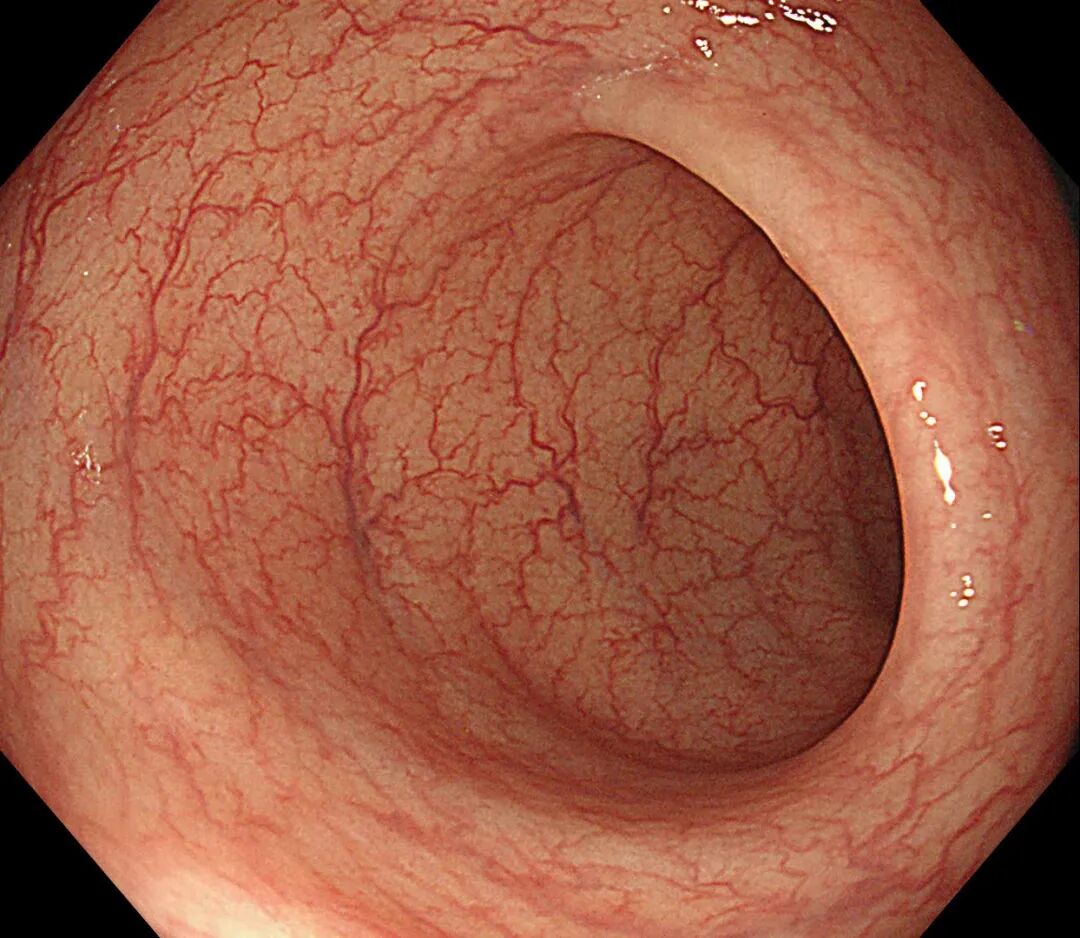

³¦¾µ½øÈ볦µÀºó£¬ÄÜÇåÎúµØ¹Û²ìÕû¸ö³¦µÀÄÚ±Ú£¬Ð¡µ½1-2mmµÄ¶«Î÷£¬ÏñСÃ×ÄÇô´óµÄÒ²ÄÜ¿´µÃ¼û¡£

×ö³¦¾µÊ±Ò½Éú½«¾µÉí´Ó¸ØÃŲåÈëÈ˵Ĵ󳦣¬²¢Ïò³¦µÀÀï³äÈë¿ÕÆø£¬Ê¹³¦µÀÀ©ÕÅ£¬ÕâÑù¾Í¿ÉÒÔÔÚÏÔʾÆ÷ÉÏÇå³þ¿´µ½³¦Ç»ÄڵĽṹ¡£Õû¸ö¼ì²é¹ý³Ì´óÔ¼»á³ÖÐø10-30·ÖÖÓ×óÓÒ£¬´ó²¿·ÖÈË¿ÉÒÔÄÍÊÜÕâ¸ö¼ì²é¡£